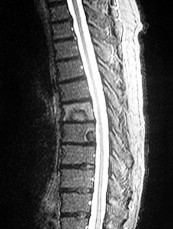

A 65-year-old male presents with classic symptoms of neurogenic claudication. He reports bilateral leg pain and fatigue that worsens with walking but is reliably relieved by leaning forward onto a shopping cart. In the pathogenesis of degenerative lumbar spinal stenosis, which structure is primarily responsible for dynamic central canal compression during spinal extension?

Explanation

In degenerative lumbar spinal stenosis, extension of the spine decreases the sagittal diameter of the canal because the ligamentum flavum buckles inward (shingling), dynamically compressing the thecal sac. Flexion of the spine pulls the ligamentum flavum taut, increasing the available canal space and alleviating neurogenic claudication symptoms. Hypertrophic ligamentum flavum is a major structural contributor to central stenosis.